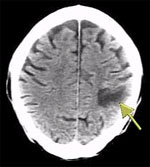

1971年,豪斯菲尔德研制成功的世界上第一台X射线计算机断层扫描机(Computerized Tomography,简称CT)在伦敦一家医院正式安装使用。X射线管在置在患者上方, 绕检查部位旋转, 患者下方的计数器也同时旋转。由于人体器官和组织对X射线的吸收程度不同,病变组织和正常组织对X射线的吸收程度也不同,这些差别反映在计数器上, 经电子计算机处理,便构成了探测对象各个部位的横断图像呈现在荧光屏上,它解决了X射线照相的前后物体图像重叠问题,大大提高了医学诊断的可靠性和准确性,使医学成像技术向前跨了一大步。豪斯菲尔德与神经放射学家阿姆勃劳斯合作,成功地为一名英国妇女诊断出脑部的肿瘤,获得了第一例脑肿瘤的照片。他们在英国放射学会上发表了第一篇论文,1973年英国放射学杂志对此作了正式报道,这篇论文受到了医学界的高度重视,被誉为“放射诊断学史上又一个里程碑”,从此,放射诊断学进人了CT时代。1979年的诺贝尔生理.医学奖破例地授给了豪斯菲尔德和科马克这两位没有专门医学经历的科学家[16]。